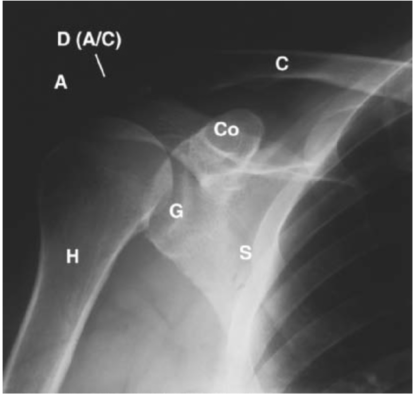

Liên hệ X quang:

- A = Acromion: Mỏm cùng vai

- C = Clavicle: Xương đòn

- Co = Coracoid process: Mỏm quạ

- D = Acromioclavicular joint: Khớp cùng vai-đòn

- G = Glenoid: Ổ chảo

- Gr = Greater tubercle of the humerus: Củ lớn

- H = Humerus: Xương cánh tay

- S = Scapula: Xương bả vai